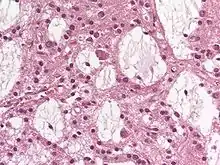

Dysembryoplastic neuroepithelial tumour (DNT, DNET) is a type of brain tumor. Most commonly found in the temporal lobe, DNTs have been classified as benign tumours.[1] These are glioneuronal tumours comprising both glial and neuron cells and often have ties to focal cortical dysplasia.[2]

Dysembryoplastic neuroepithelial tumours are largely glioneuronal tumours, meaning they are composed of both glial cells and neurons.[2]